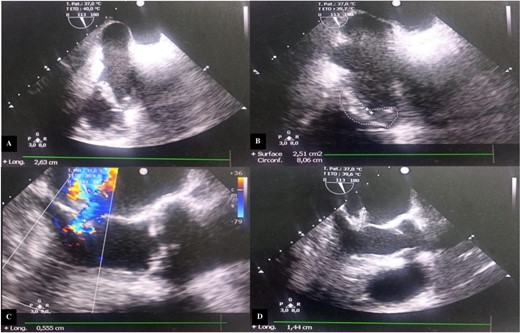

We performed an annular suture, followed by suturing the papillary muscles into the right ventricle: the anterior papillary muscle to the interventricular septum and the posterior papillary muscle to the posterior tricuspid papillary muscle. The repair was consolidated with a tricuspid annuloplasty ring (size 32; Carpentier-Edwards) (Fig. 3). Cultures of the resected segments were negative. Post-operative follow-up was uneventful, and echocardiographic follow-up at discharge showed no residual tricuspid regurgitation or stenosis (Fig. 4).

Postoperative transthoracic echocardiography, four chambers showed at 1 month. Green arrow: mechanical mitral prosthesis in place without stenosis and without detectable leakage. White arrow: tricuspid coaptation without detectable leakage, with slight excess fabric at the suture line on the anterior tricuspid leaflet. Blue arrow: inferior tricuspid papillary muscle. Red arrow: anterior tricuspid papillary muscle.

At the 18-month follow-up, the patient was in NYHA class I, and TTE showed mild tricuspid regurgitation. The mean pulmonary artery pressure had decreased to 18 mmHg.